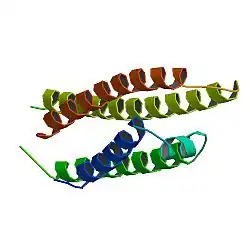

Vektorisierung

Ein anderer Weg, um die Blut-Hirn-Schranke mit einem Wirkstoff zu überwinden, ist die Vektorisierung.[42] Dieser Ansatz beruht auf der Beobachtung, dass einige Makromoleküle, wie Transferrin,[43] Low Density Lipoprotein[44] und Insulin[45] über einen mehrstufigen, als rezeptorvermittelte Transzytose bezeichneten Prozess die Blut-Hirn-Schranke überwinden können. Über Rezeptoren, die sich an der Oberfläche der Endothelzellen der Hirnkapillaren befinden und in das Lumen der Blutgefäße hineinragen, werden die Makromoleküle in das Innere der Endothelzellen über Vesikel eingeschleust, um dann auf die andere Seite der Zelle (abluminale Seite) transportiert und ausgeschleust zu werden. Wird ein Wirkstoffmolekül an ein solches Makromolekül gebunden, kann die rezeptorvermittelte Transzytose zur Überwindung der Blut-Hirn-Schranke ausgenutzt werden.

Ein Beispiel hierfür ist der Transferrinrezeptor, der mit Hilfe gegen ihn gerichteter monoklonaler Antikörper zum Transport von Wirkstoffen durch die Blut-Hirn-Schranke genutzt werden kann. Dieser Rezeptor ist gewöhnlicherweise für den Transport von Eisen durch die Blut-Hirn-Schranke zuständig.[46][47] Ein anderes Target ist der Insulinrezeptor, der auch von den Endothelzellen der Blut-Hirn-Schranke exprimiert wird.[48] Mit beiden Vektoren wurden im Tiermodell verschiedene, auch größere, Peptide erfolgreich über die Blut-Hirn-Schranke geschleust.[49] Speziell für die Therapie von neurodegenerativen Erkrankungen, für die nur geringe Wirkstoffkonzentrationen notwendig sind, ist die Vektorisierung ein vielversprechender Ansatz.[50][51] Auch Zytostatika wie beispielsweise Doxorubicin wurden an Transferrinrezeptor-Antikörper gebunden.[52]